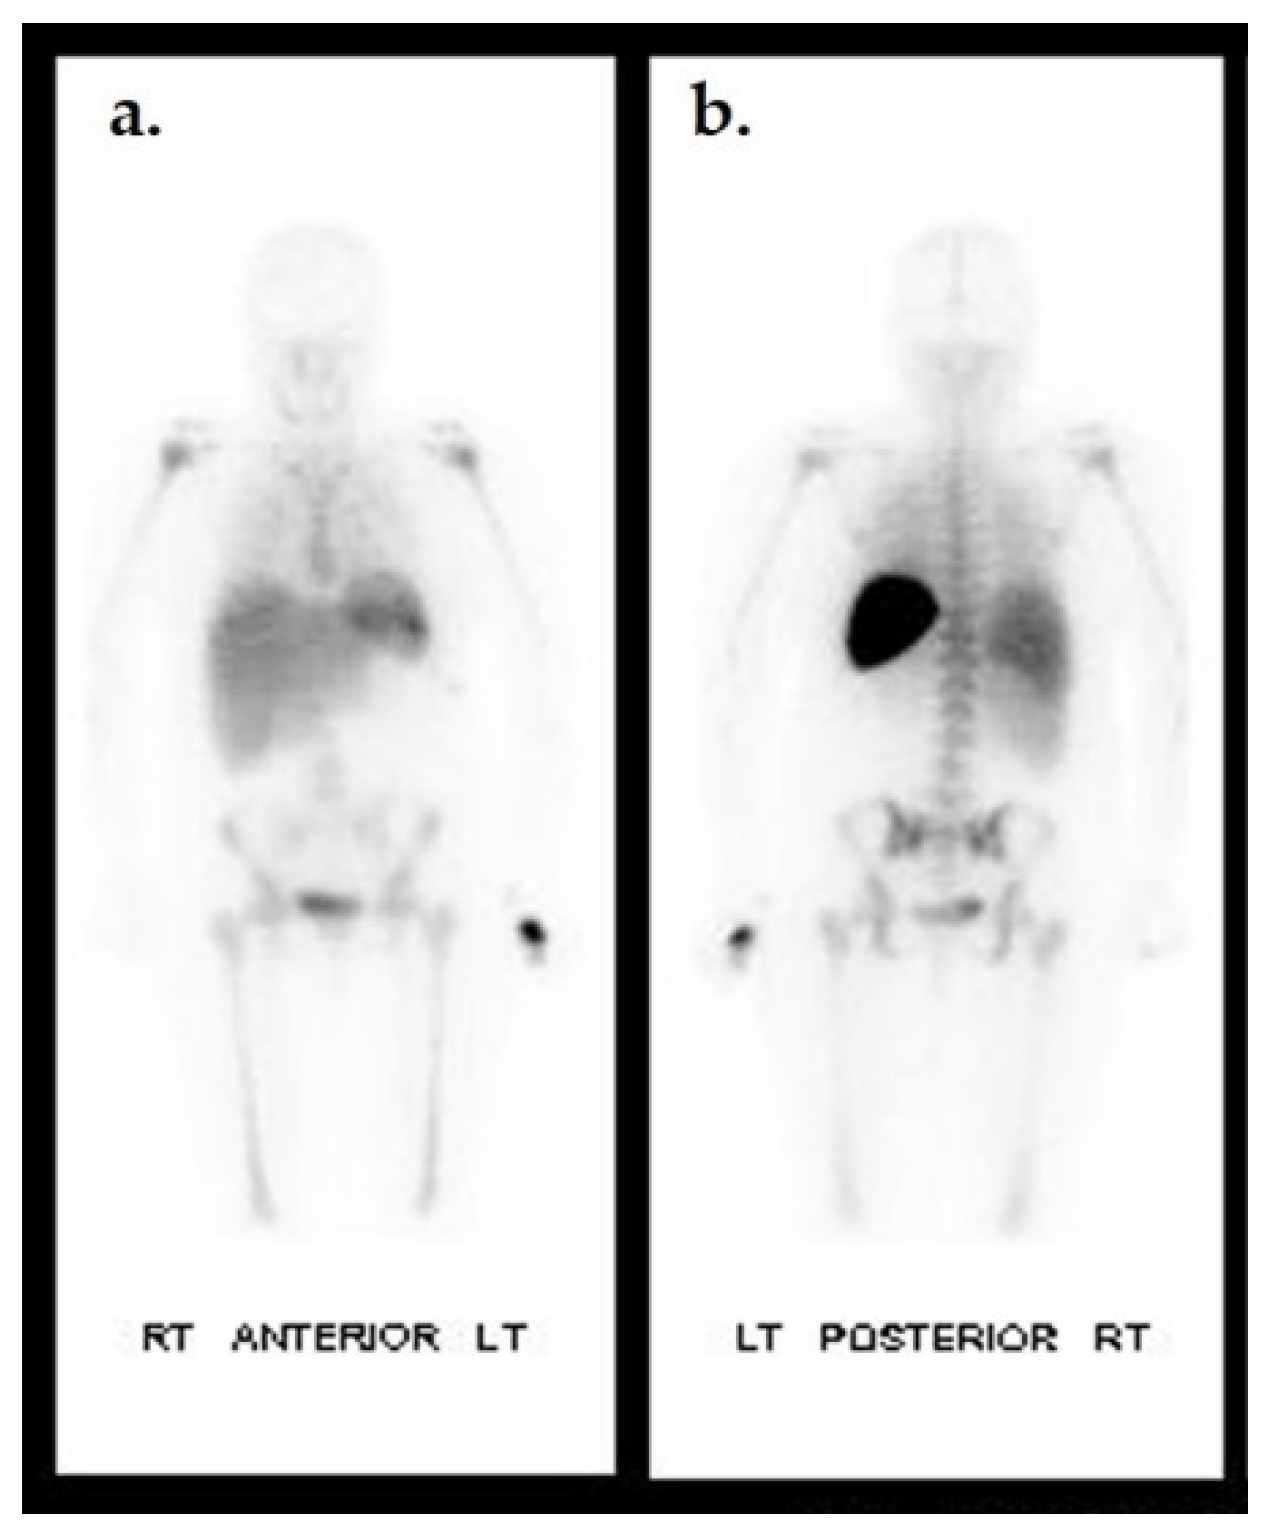

- Ruotolo, V.; Di Pietro, B.; Giurato, L.; Masala, S.; Meloni, M.; Schillaci, O.; Bergamini, A.; Uccioli, L. A new natural history of Charcot foot: Clinical evolution and final outcome of stage 0 Charcot neuroarthropathy in a tertiary referral diabetic foot clinic. Clin. Nucl. Med. 2013, 38, 506–509. [Google Scholar] [CrossRef]